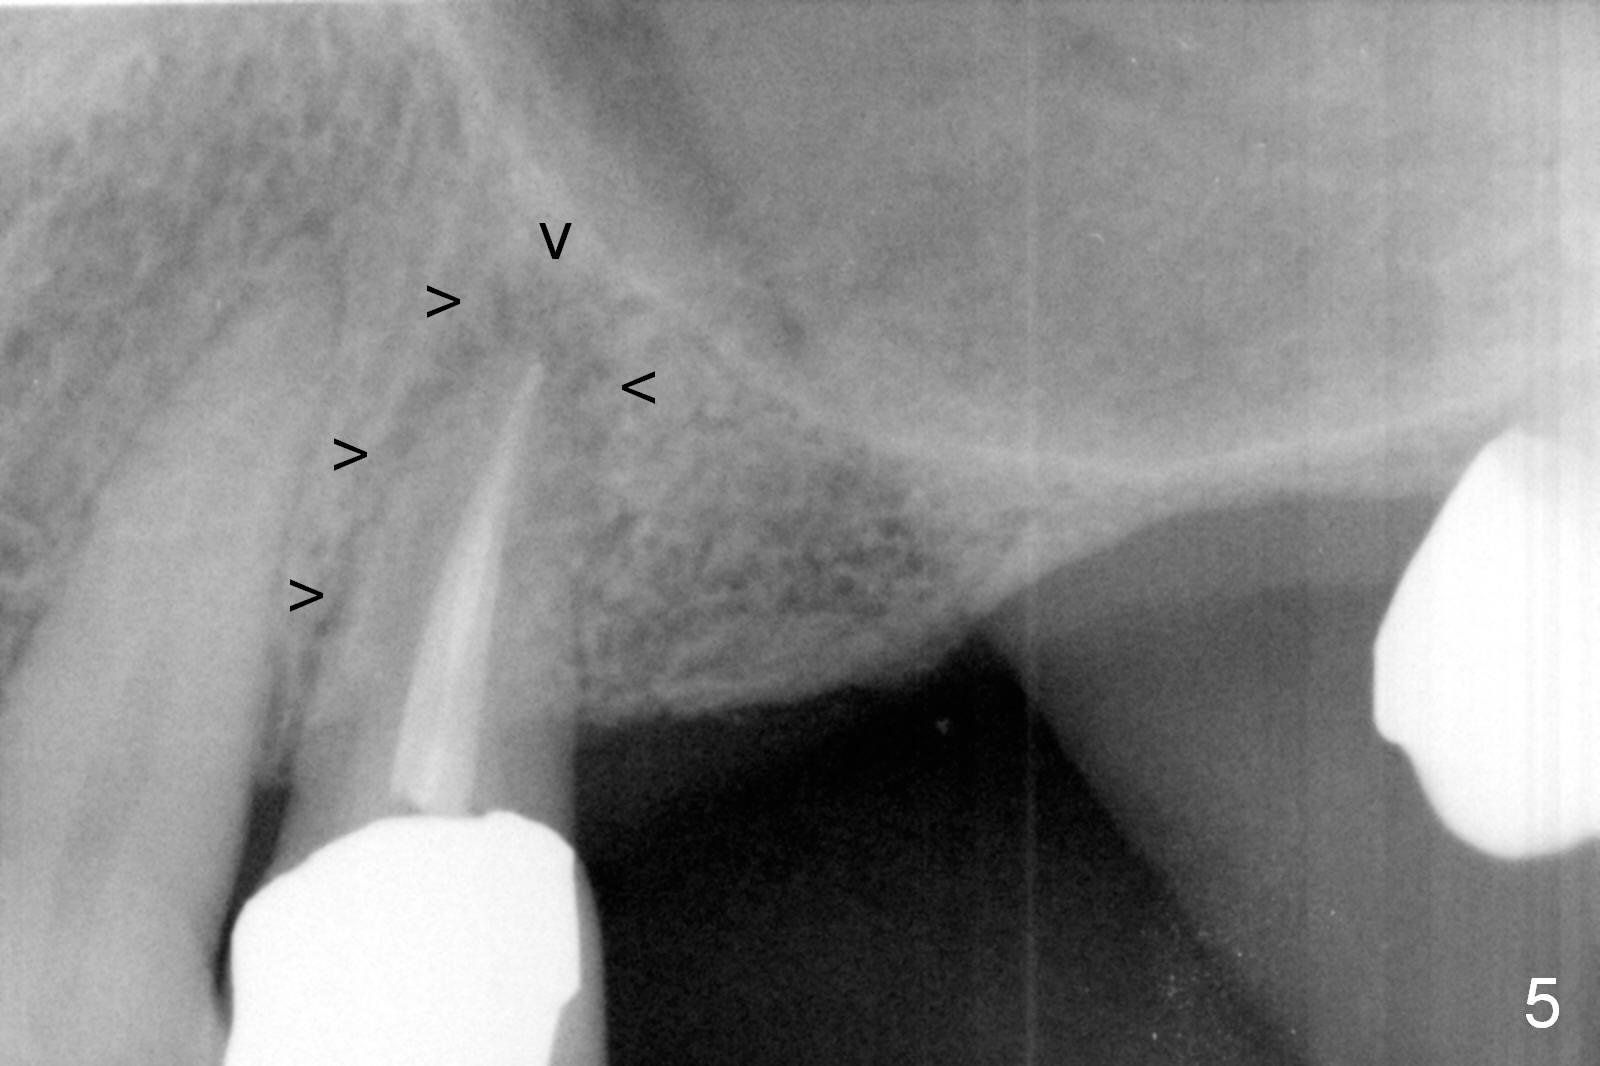

A 64-year-old man (MM) had caries at the tooth #12 (Fig.1), requiring root canal therapy (RCT, Fig.2). One year later, the periapical radiolucency reduces (Fig.3 <, as compared to that in Fig.2). The tooth remains asymptomatic 7 years posts RCT (Fig.4). A year later, the tooth has pain and buccal gingival swelling (probing tenderness); periradicular radiolucency is evident (Fig.5 arrowheads). It appears that the root fractures. Between the 7th and 8th years post RCT, the patient masticated mainly on the left side, while implants were placed at #30 and 31. The patient plans to have 4 implants in the upper left sextant (Fig.6). While implants are being placed at the site of #12 (Clindamycin) and 13, sinus lift seems mandatory at the sites of #13 and (initial depth will be 5-6 mm). By the time implants to be placed at #14 and #15, the bone height may increase.

Impression has been taken for wax up. The root fracture at #12 is obvious now. Take photos.